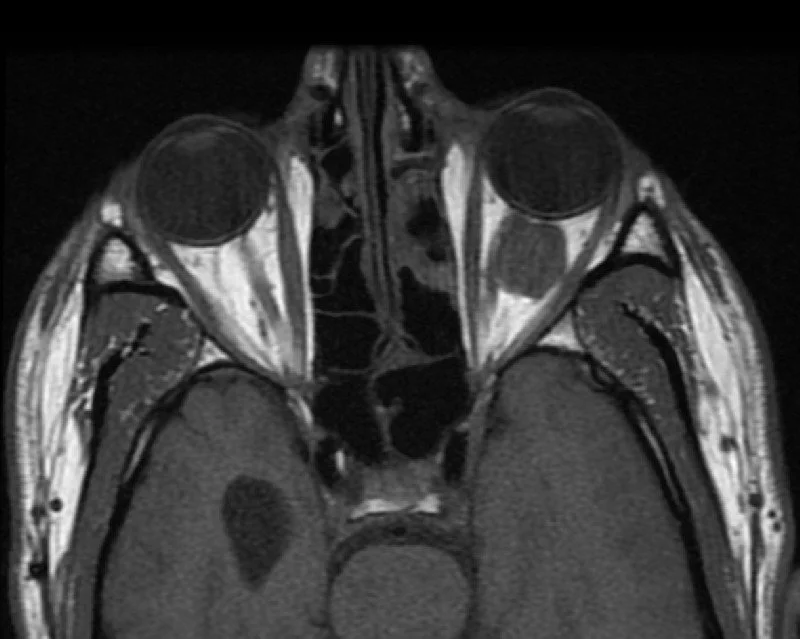

• Basically hemangioma of the eye - but no true epithelial capsule and technically not a neoplasm

• >80% are intraconal, typically laterally located

• Presents with proptosis and can cause local compression - eye issues